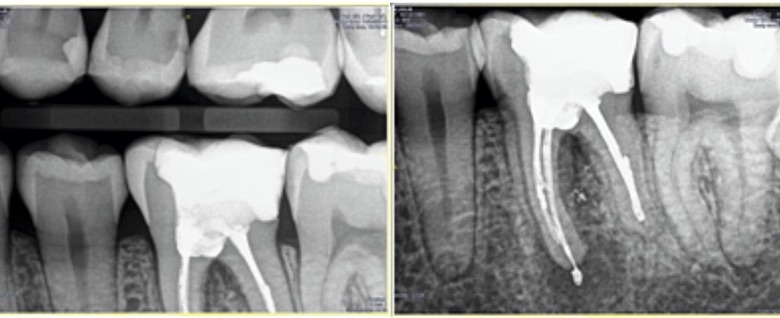

Fig. 2. Radiografía de aleta de mordida y periapical inicial.

Fig. 7. Radiografía final del retratamiento no quirúrgico del 3.6. con su restauración indirecta cementada.